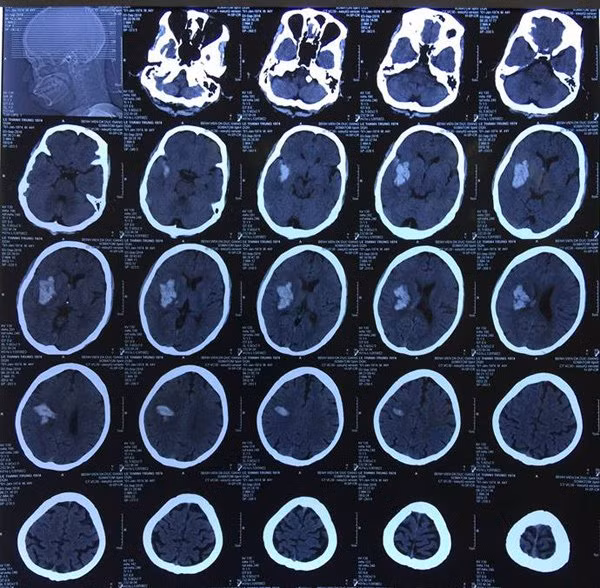

Bệnh nhân Lê T.T. (44 tuổi, Gia Lâm, Hà Nội) đến BV đa khoa Đức Giang khám do đột ngột đau đầu, nói ngọng. Bệnh nhân đã được các bác sĩ thăm khám, chụp CT sọ não, phát hiện trong não có khối máu tụ.

Tuy nhiên sau nhập viện, tình trạng bệnh nhân xấu đi rất nhanh, rơi vào trạng thái hôn mê kèm liệt nửa người trái. Kết quả chụp CT sọ não lần 2 cho thấy khối máu tụ trong não đã lan rộng, kích thước gấp 3-4 lần so với ban đầu, gây chèn ép các tổ chức xung quanh, sức khoẻ nguy kịch.

| Hình ảnh khối máu tụ trong não bệnh nhân |